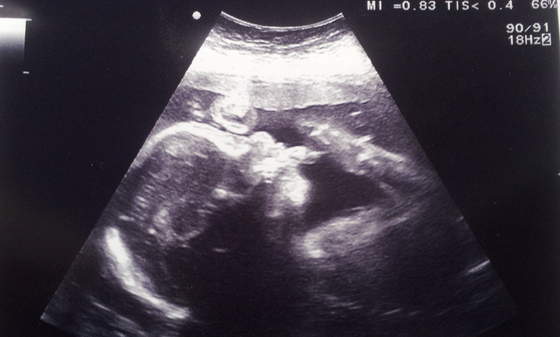

To jest Mateusz drugi do wyjscia z kciukiem w buzi

20120922_160614.jpg